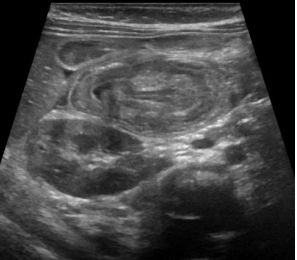

198. 1 歲男童,因腹痛及嘔吐被帶來兒童急診就診,身體診察腹部柔軟,床邊 超音波影像如下,下列敘述何者較適當? (A)診斷為幽門阻塞,應會診消化外科,進行幽門切開術。 (B)診斷為急性闌尾炎,需會診消化外科手術。 (C)診斷為腸套疊,可先使用生理食鹽水或空氣顯影灌腸。 (D)診斷為先天性腸扭轉,需剖腹探查。